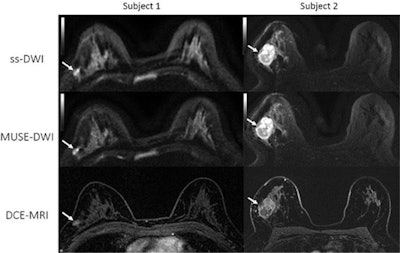

The future of DWI-MRI for breast imaging may not be far off, either. In May, researchers detailed how they repurposed a DWI-MRI protocol originally designed for brain imaging. The multiplexed sensitivity-encoding (MUSE) protocol resulted in better image quality and improved signal-to-noise ratio for breast lesions.

Comparison of single-shot (ss) DWI, MUSE DWI, and dynamic contrasted-enhanced (DCE) MRI axial images for two patients with biopsy-proven invasive ductal carcinoma. Image courtesy of the RSNA."MUSE DWI yielded significantly improved image quality compared with single-shot DWI in phantoms and participants," the team wrote.